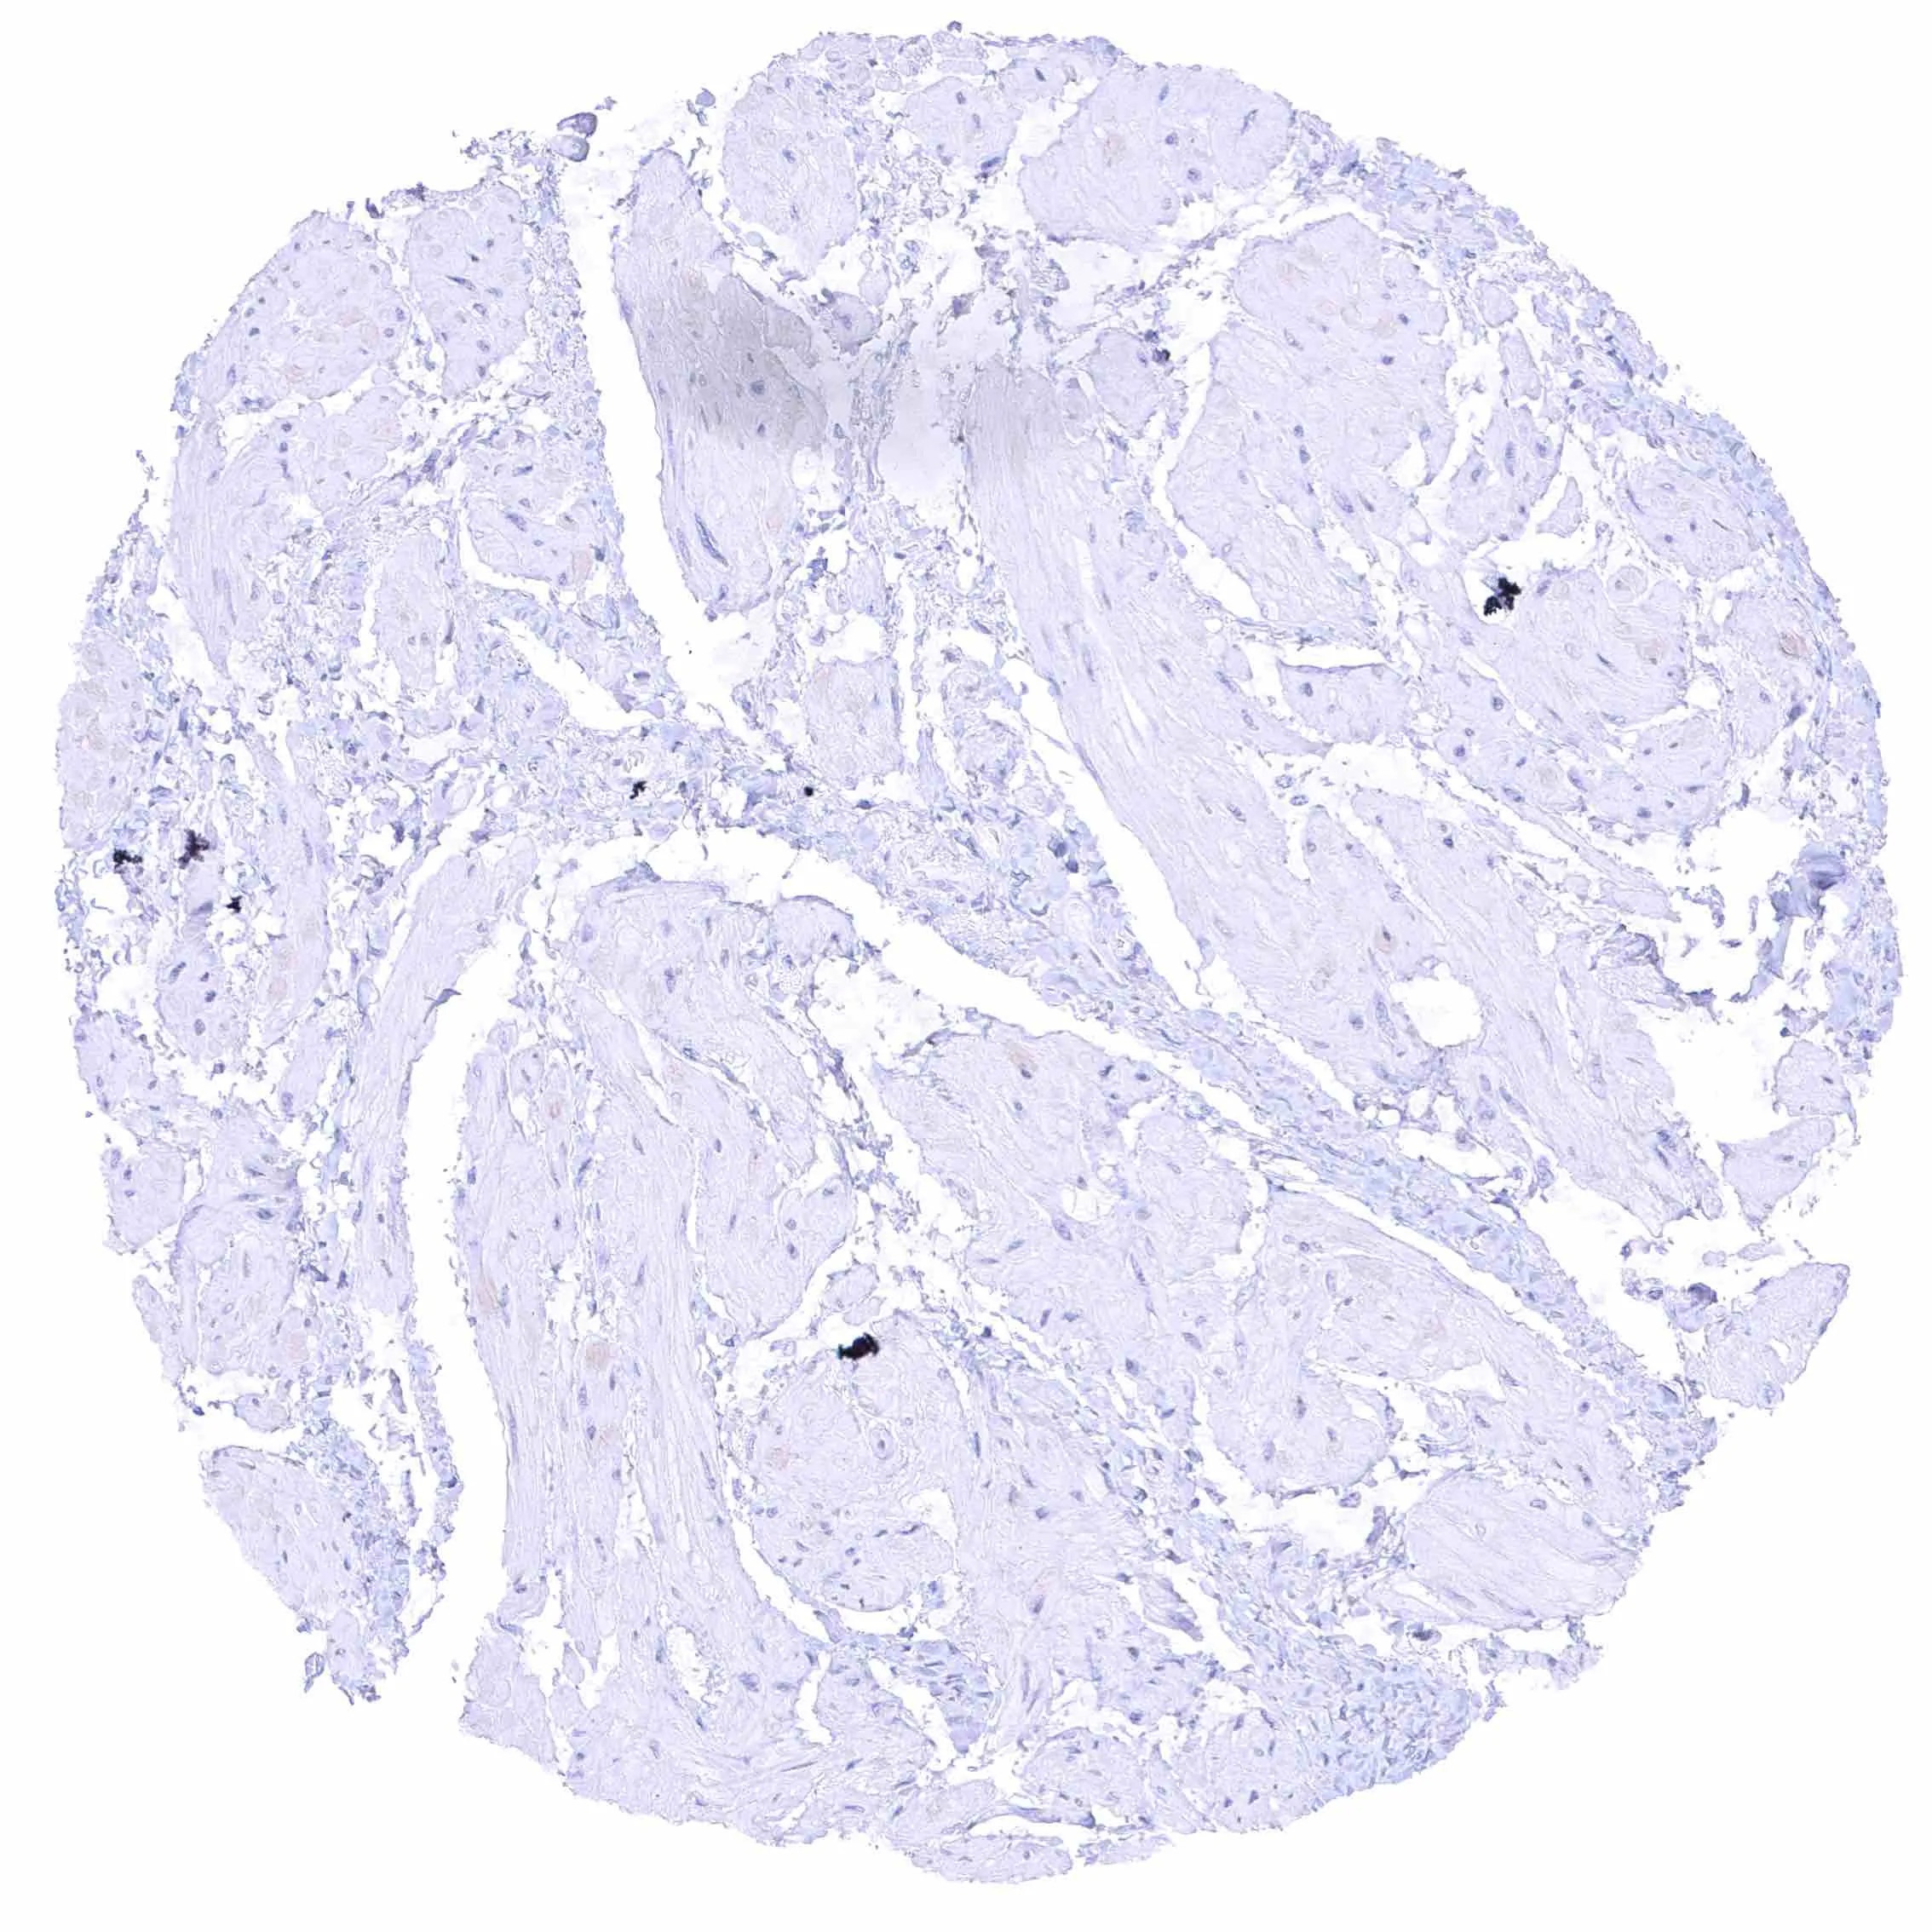

Uterus, myometrium – Distinct NPR-C staining of endothelial cells in some but not all blood vessels